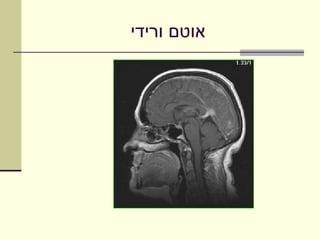

‫אוטם ורידי‬

‫סתימה ורידית גוררת סטזיס‬   ‫‪‬‬

‫של דם וירידה באספקת‬

‫חמצן לרקמת המח‬

‫טשטוש חריצים בהמיספרה‬     ‫‪‬‬

‫שמאלית‬